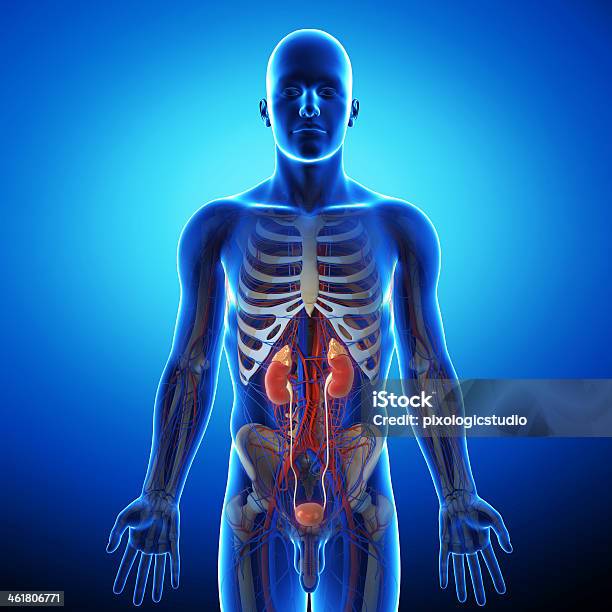

Diagram Of Prostate Background Stock Photos, Pictures & Royalty-Free …

Urinary Tract Anatomy Pictures, Images and Stock Photos – iStock

Scientific Publishing The Urinary System Chart

The Urinary System: Ureter and Urinary Bladder